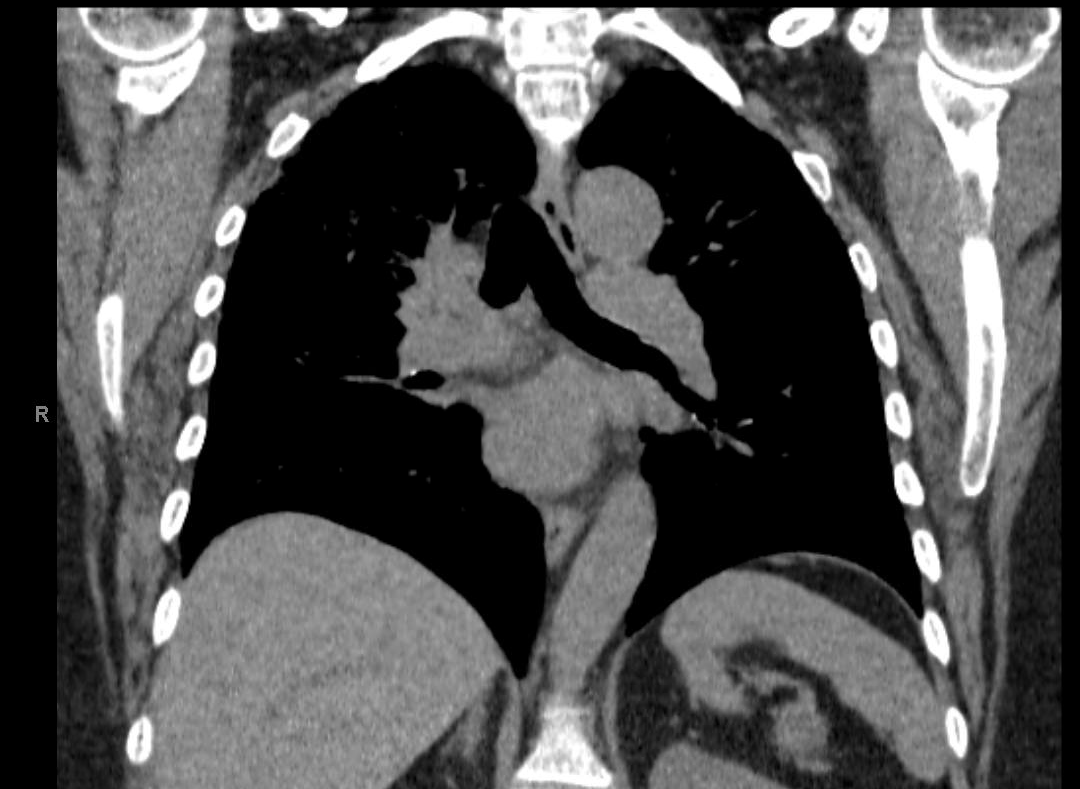

A boy was born via normal spontaneous vaginal delivery at 36 weeks and 1 day of gestation to a 20-year-old, gravida 1, para 1 woman. At 9 hours of life, a neonate presented with a large emesis, this time...